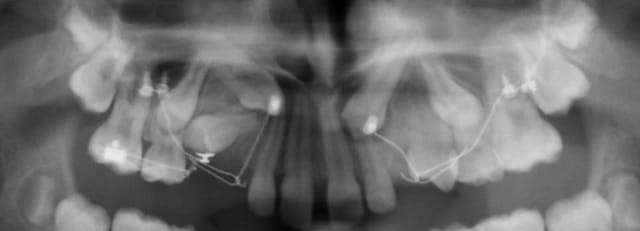

Et voilà, aujourd'hui ça fait cinq mois jour pour jour que la mécanique est en place, la 14 est arrivée en occlusion.

23 a très bien progressé également.

Reste le problème de l'apex de 14 qu'il convient de distaler pour permettre à la 13 de passer.

Je ne veux interférer sur la tension du CT8 de la 13, je n'ai pas envie non de faire un arc transpalatin comme le suggérait notre ami Seespan.

Que puis-je alors faire de simple et rapide à mettre en place) ?

12224 3 jspjy6 - Eugenol